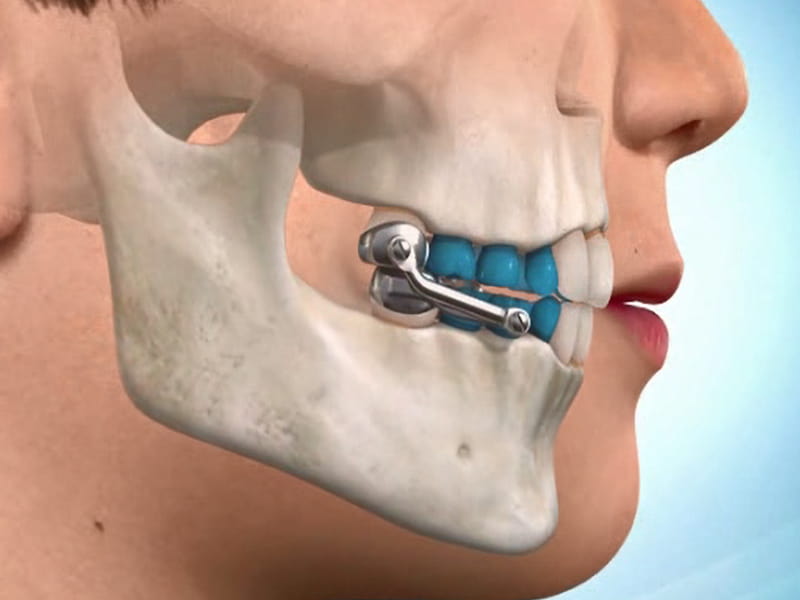

در این روش، ایمپلنت زیر لثه کاشته میشود و به فک متصل میشود.

سپس، برای اصلاح زاویه فک و تعامل بین فکها، از پروتکلهای درمانی خاصی استفاده میشود که شامل تنظیم فشار و قدرت ایمپلنت، استفاده از براکتها و وسایل جانبی دیگر است.

این ایمپلنت زیر لثه کاشته میشود و به فک متصل میشود.

دارای قابلیت تنظیم بالاست و میتواند برای اصلاح زاویه فک و تعامل بین فکها، از پروتکلهای درمانی خاصی استفاده کند.